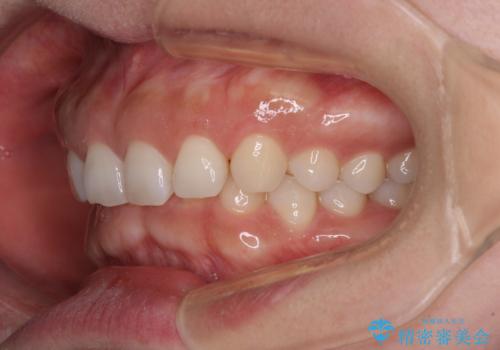

【モニター】ディープバイトを治す ワイヤー装置による矯正治療

手前に傾斜している奥歯を直立させながら、歯列全体の平面を均一に整えることでディープバイトを改善していくこととしました。

ディープバイトは咬合力が強いことが特徴であり、より良い仕上がりとするために、臼歯部のコントロールを行いやすいワイヤー装置を用いて矯正治療を行うこととしました。